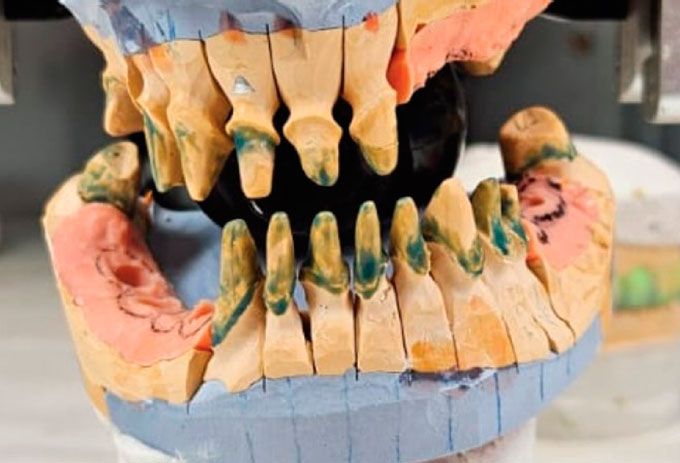

Изготовлены разборные гипсовые модели верхней и нижней челюсти (рис. 16).

Рис. 16. Разборные гипсовые модели верхней и нижней челюсти

Fig. 16. Split casts of the maxilla and mandible